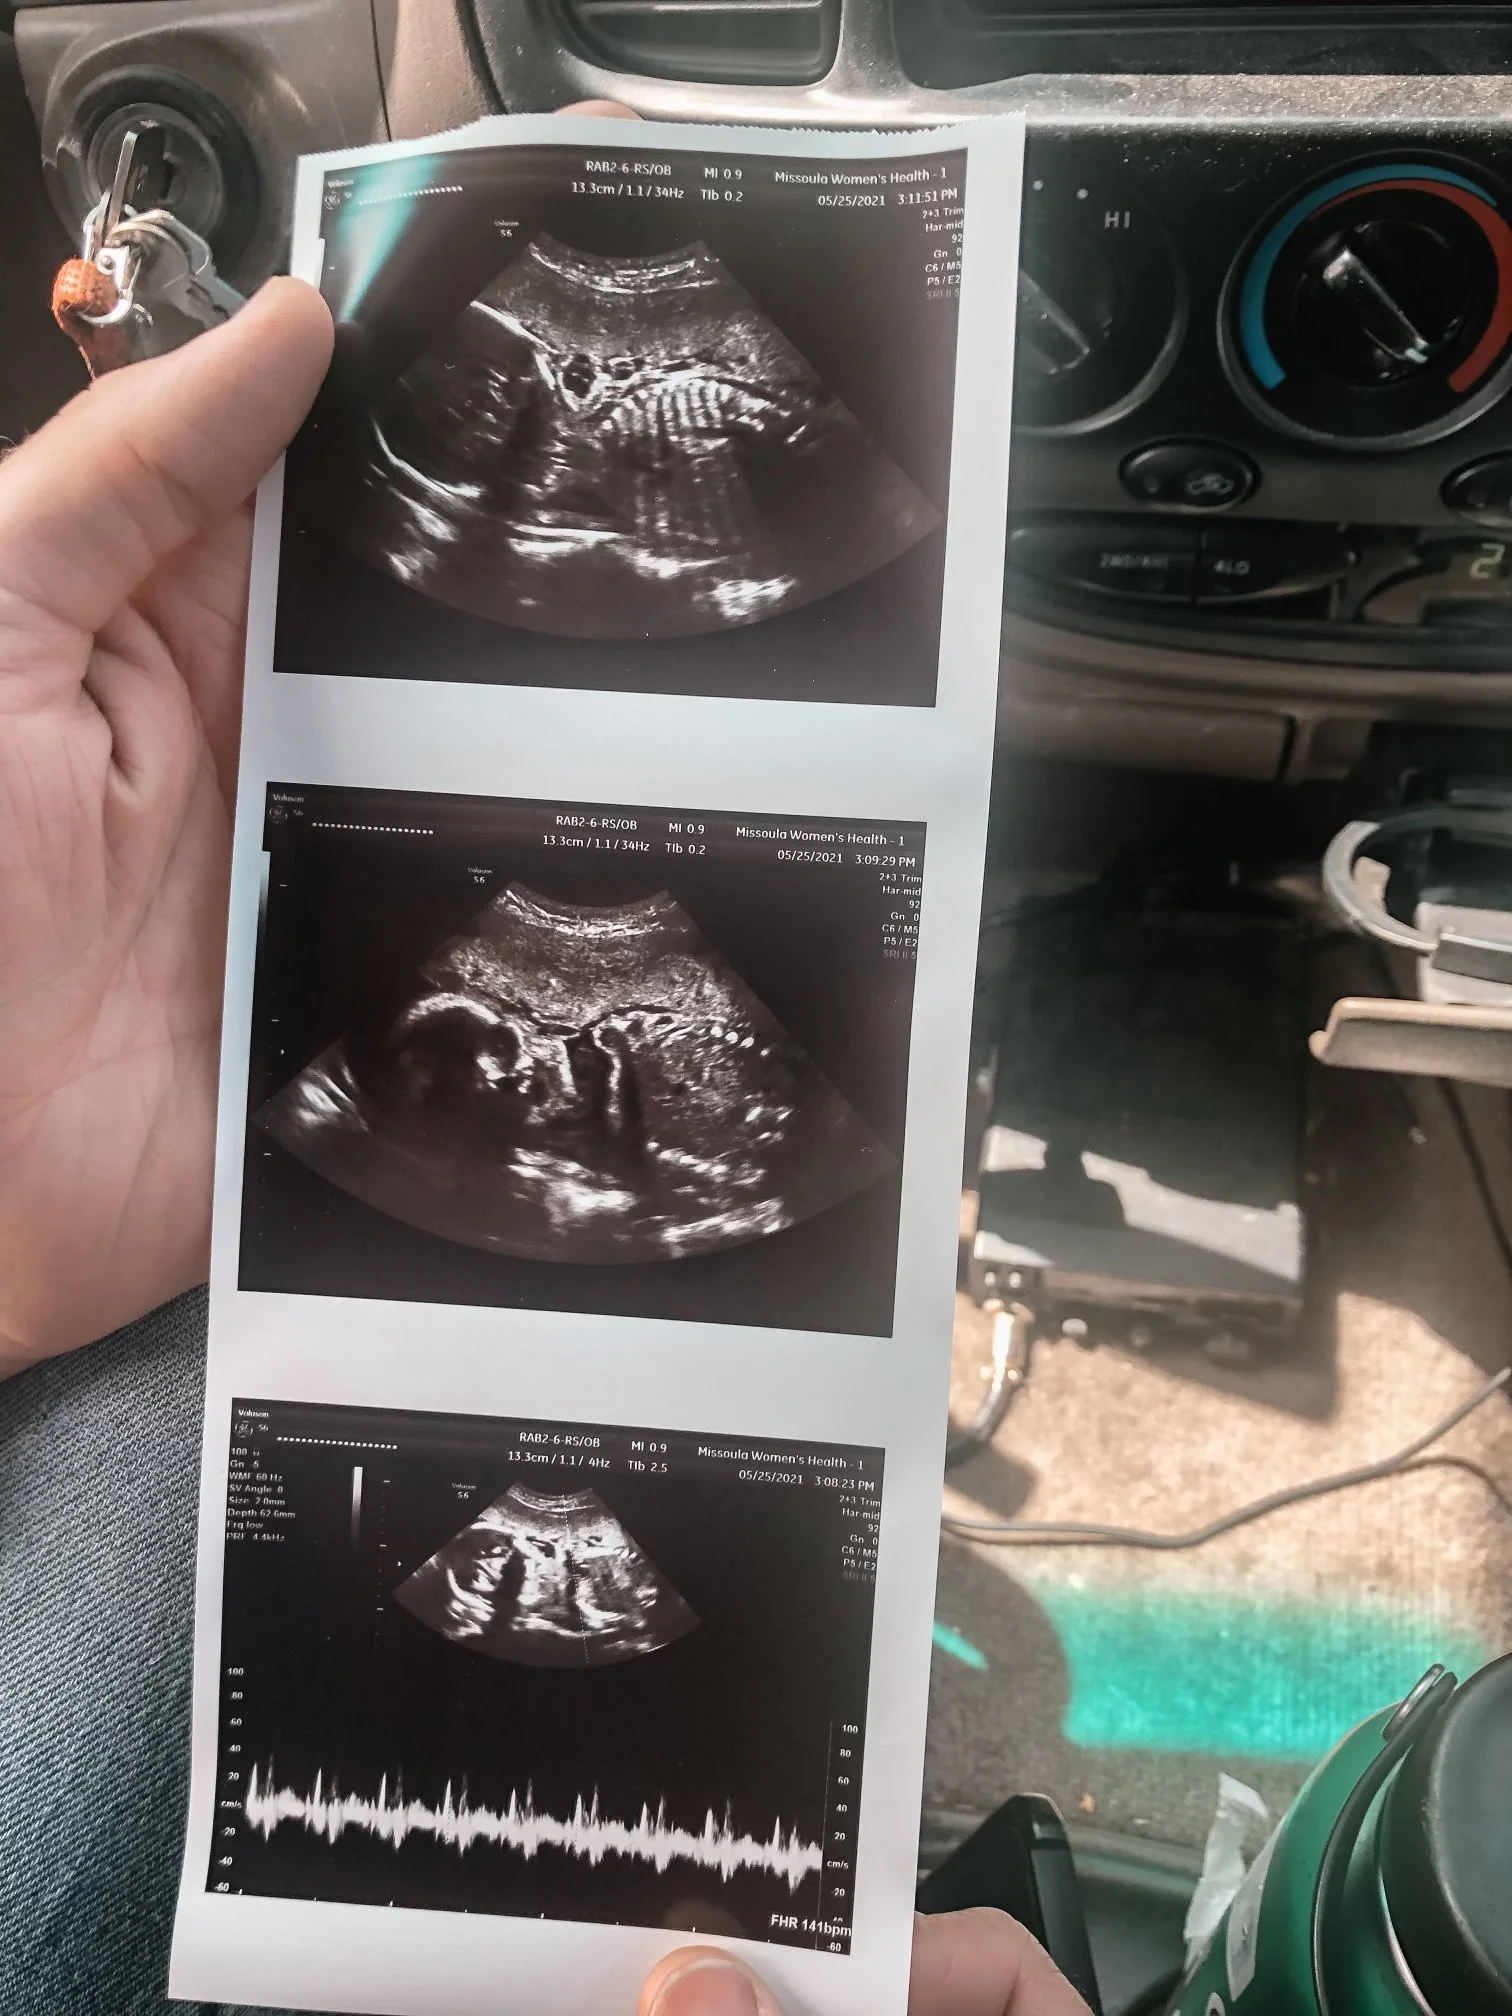

My pregnancy was normal for the first 20 weeks with Noah. I had all the classic symptoms and revelled in them since I had had none with the miscarriage. That lasted 2 weeks. The next 14 weeks I hated all the symptoms. I loved our OB and I loved getting to see our little bean on the ultrasound. I remember going in for my 20 week ultrasound and the nurse practitioner said they found an Echogenic Intracardiac Focus (EIF) on the heart. She mentioned this could be a marker for Down Syndrome. Insert emotional spiral. I remember calling my doctor immediately and asking him about this. He calmed me down and assured me that he had never had a Down Syndrome diagnosis with only one marker. I remember feeling immediately relieved that we weren’t having a child with Down Syndrome.

Flash forward to 34 weeks. I had a follow up with maternal fetal medicine (because I am old) and they said it looked like the baby was having Intrauterine Growth Restriction (IUGR). The sepcialist seemed concerned but not worried. I reached out to my sister who is a nurse and she reassured me it was nothing to worry about. The doctor wanted me to come back for two scans a week until my due date or until he found a reason I needed to be induced. Well, at 37 weeks he found a reason for me to be induced, my amniotic fluid was low and decreasing quickly. He told me it would be best to get induced that day. My appointment was before work and I stupidly asked if I could go back to work for the day and start the induction that evening. I don’t know why I asked, maybe I felt like I needed more time to process. We were going to meet our BABY!